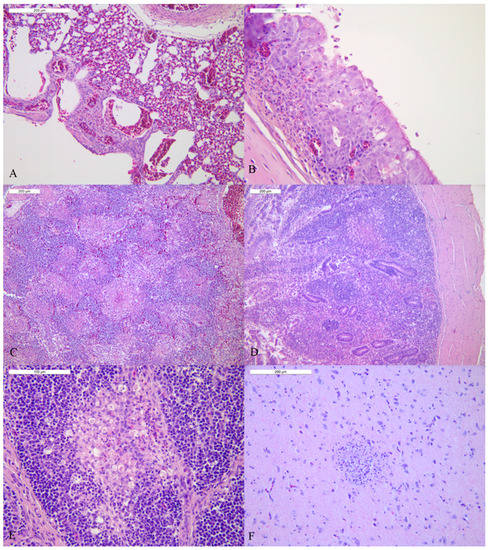

3.4. Study of Tissue Tropism and Pathogenesis (Pathobiology of HPAI Infection)

| Lung | 17.6 | +++ | 34.01 | − | 21.06 | +++ | 18.77 | +++ | 18.43 | +++ | Pneumocytes, endothelium |

| Trachea | 18.9 | + | 27.89 | − | 21.67 | ++ | 21.96 | ++ | 19.77 | +++ | Epithelial cells, macrophages, endothelium |

| Spleen | 19.07 | + | 36.13 | − | 19.81 | +++ | 22.08 | ++ | 23.32 | ++ | Macrophages, endothelium |

| Duodenum | 18.35 | ++ | 31.32 | − | 22.39 | + | 21.36 | + | 20.09 | +++ | Cellular debris in the crypts, epithelium, endothelium and plexi |

| Pancreas | 17.17 | +++ | 33.57 | − | 22.19 | ++ | 22.21 | + | 18.73 | +++ | Acinar necrotic epithelium |

| Cecal tonsil | 16.81 | +++ | 25.32 | + | neg | n.d. | 22.46 | ++ | 18.29 | ++ | Cellular Debris in the crypts, epithelium, necrotic area, endothelium |

| Bursa of Fabricius | 18.19 | +++ | 32.91 | − | 20.25 | + | 21.71 | ++ | 15.15 | ++ | Macrophages |

| Brain | 13.85 | +++ | 34.6 | − | 19.83 | ++ | 17.2 | +++ | 18.94 | +++ | Neurons, glial cells, ependymal |

| Lung | neg | − | neg | n.d. | neg | n.d. | 25.03 | −/+ | 39.43 | − | Pneumocytes |

| Trachea | 37.68 | − | neg | n.d. | neg | n.d. | 23.83 | + | 38.46 | − | Epithelial cells, macrophages |

| Spleen | neg | n.d. | neg | n.d. | neg | n.d. | 23.86 | −/+ | neg | n.d. | Macrophages |

| Duodenum | neg | n.d. | neg | n.d. | neg | n.d. | 25.03 | −/+ | neg | − | Epithelium |

| Pancreas | neg | n.d. | neg | n.d. | neg | n.d. | 24.03 | −/+ | 38.31 | − | Acinar necrotic epithelium |

| Cecal tonsils | neg | n.d. | neg | n.d. | neg | n.a. | 24.05 | + | neg | n.d. | Debris in the crypts, epithelium, necrotic area, endothelium |

| Bursa of Fabricius | neg | n.d. | neg | n.d. | neg | n.a. | 22.25 | − | neg | n.a. | n.a. |

| Brain | neg | n.d. | neg | n.d. | neg | n.d. | 19.88 | + | neg | n.d. | Neurons, glial cells, ependymal |